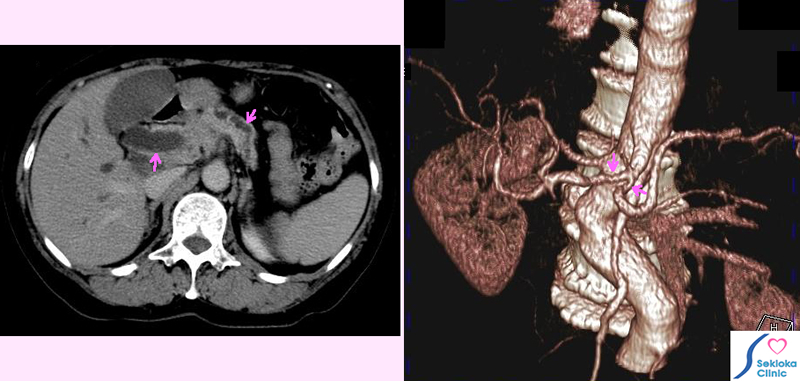

膵臓がんCT

自覚症状  黄疸に気づき、来院

超音波エコーで胆管、膵管の拡張と膵臓頭部の腫大認め、膵臓がん疑い

造影CT検査施行。腹腔動脈などへのがんの浸潤認めました。

血管への浸潤が既にあるため、手術による摘出は困難と判断され、黄疸治療

のため総胆管へのステント挿入。化学療法後、保存的治療。